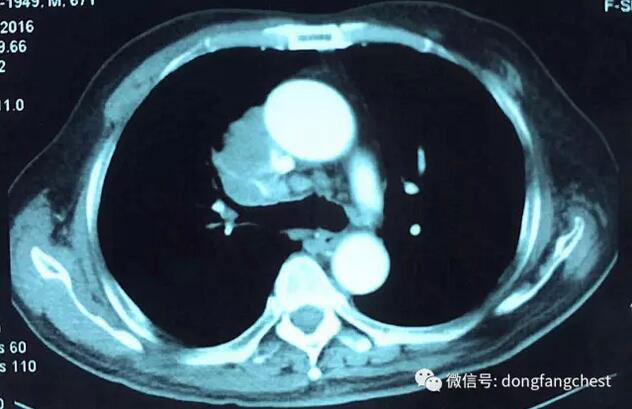

年近70岁的李老爷子,反复咳嗽了一个月不见好,于2016年12月在东方总院拍CT,检查发现”右肺上叶恶性肿瘤“。

由于肿瘤体积较大,且与肺动脉、上腔静脉关系紧密,手术实施起来较为困难,经过东方总院多学科讨论会诊,决定先于呼吸内科进行了2个疗程新辅助化疗。

化疗后,李老体内的肿瘤体积明显缩小,随后于2月22日进入总院心胸外科进行手术治疗。手术由总院胸外科朱胜主任、王鸿副主任、高涛涛医生共同完成。术中发现肿瘤侵犯右肺动脉干、上腔静脉部分血管壁。术中,经上腔静脉远端、右心房插管转流,阻断受肿瘤侵犯部位腔静脉后予以部分血管壁切除,然后取心包组织进行上腔静脉修补重建。